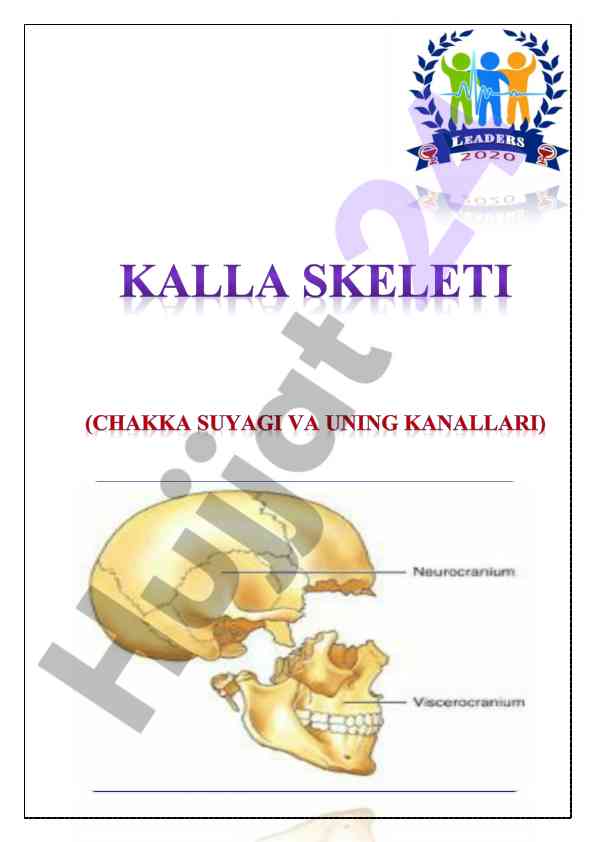

Kalla skeleti va chakka suyagi haqida umumiy ma'lumotlar taqdim etilgan o‘quv qo‘llanma. Anatomiyaga oid asosiy tushunchalar va strukturalar izohlangan.